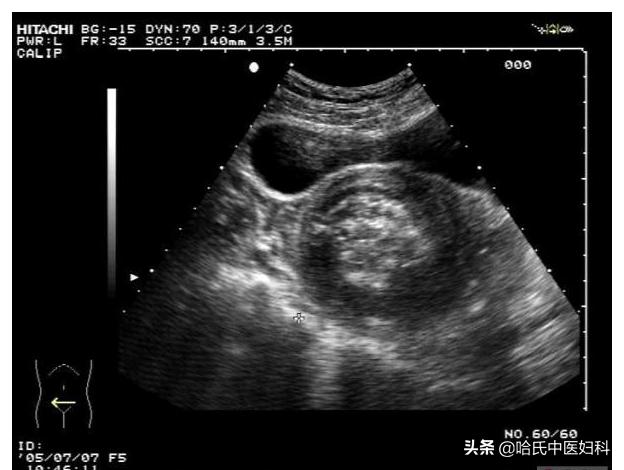

患者小徐,拿着化验单难受得直掉眼泪。四个月前,她因为有备孕需求来做检查,宫腔里有一个32*40*30mm的小肌瘤,因为肌瘤小,且无疼痛,非经期出血等异常,并没有过多治疗。

四个月后来医院复查子宫肌瘤已经到77×100×90mm,我看着化验单,询问着她的情况。

小徐知道后火冒三丈,月经不调,非经期出血。受了这么多委屈,生了这么多气,那肌瘤可不长这么大嘛!